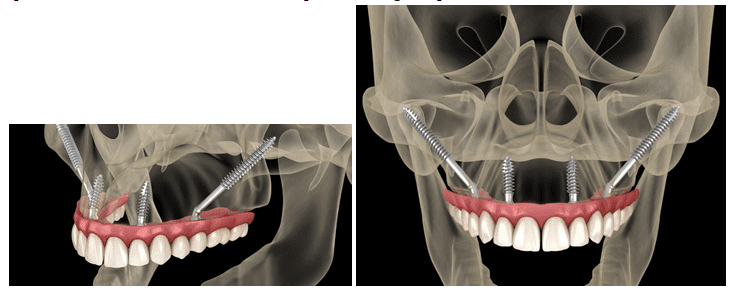

4. Zygomatic Implants:

Zygomatic implants are a specialized type of dental implant designed for patients who have severe bone loss in the upper jaw, particularly in the area of the maxillary sinuses. Instead of anchoring into the jawbone, zygomatic implants are anchored in the dense zygomatic bone, which provides exceptional stability and support. This approach eliminates the need for bone grafting procedures and allows for the immediate placement of prosthetic teeth, offering a quicker and more efficient treatment option for eligible patients.